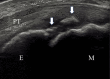

Methods: The study participants were junior baseball players who participated in a medical checkup in 2020. We included knees in the apophyseal stage evaluated using ultrasonography, and classified them into the bursitis and no-bursitis groups using color-enhanced Doppler ultrasonography. We also investigated bone lesions of the tibial tuberosity, determined by fragmentation of the bone and irregularity of the ossification center. Demographic data, practice duration, pressure pain on tuberosity, pain while playing baseball (visual analog scale), heel-buttock distance (HBD), straight-leg raise angle, and range of hip internal and external rotation were evaluated. Group comparisons were performed using the Mann-Whitney U test and Fisher exact test, and a logistic regression analysis was performed.